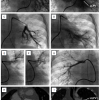

Selective or non-selective pulmonary artery wedge angiograms can be a productive place to start following collection of haemodynamic data and are often highly informative as to the site, number and severity of stenoses. An angiogram can be performed with a balloon wedge catheter, a pigtail catheter or a multipurpose catheter either in each pulmonary artery separately or in each individual lobar branch. Layered neat non-ionic contrast media (10 mls) with either saline or aspirated blood (10 mls) can be injected rapidly by hand (20 mls leurlocked syringe) to define the course of the pulmonary venous return. These images are usually best acquired straight anteroposterior and straight lateral until the site of obstruction is defined ( Figure 1 ).

Angioplasty should increase the diameter of the narrowed lesion by a factor of 3, aiming to achieve a size similar to the distal vessel diameter if possible ( Figure 5 ). This might involve using a smaller balloon followed by a larger one. The first inflation is useful in assessing the recoil of the vessel and the likelihood of achieving a good result with angioplasty alone. Again, coronary balloons are particularly useful in small infants though other non-compliant larger balloons will be required in larger patients (for example Balt Cristal [Synapse, Dublin, Ireland] and Opta® pro non-compliant balloons [Cordis, Johnson & Johnson, Warren, NJ, USA] amongst others).